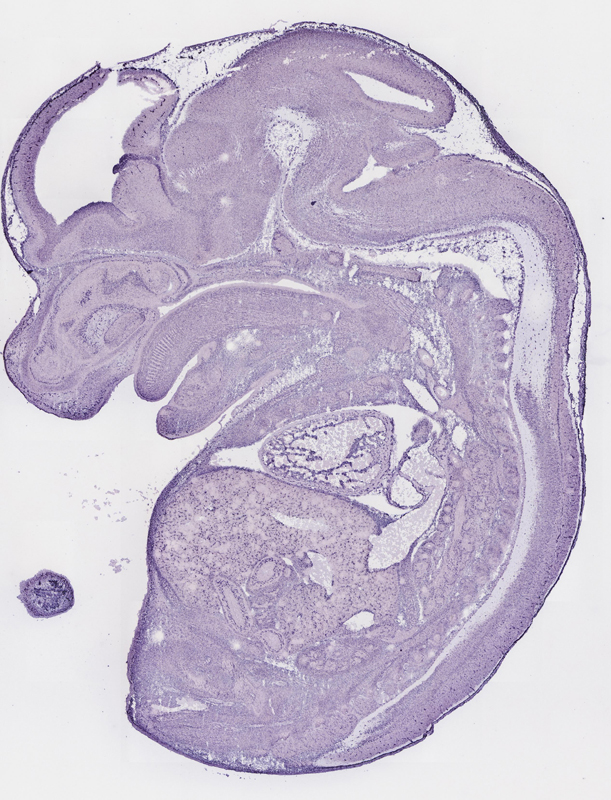

Reference: J:153498 Diez-Roux G, et al., A high-resolution anatomical atlas of the transcriptome in the mouse embryo. PLoS Biol. 2011;9(1):e1000582

Assay type: RNA in situ

Gene symbol: Mest

Gene name: mesoderm specific transcript

Assay notes: Cryosections of fresh frozen material were fixed in 4% paraformaldehyde for 20 min. before further processing. A tyramide-biotin/streptavidin amplification step was included in the in situ hybridization procedure.

Specimen euxassay_003445_04: embryonic day 14.5 (more )